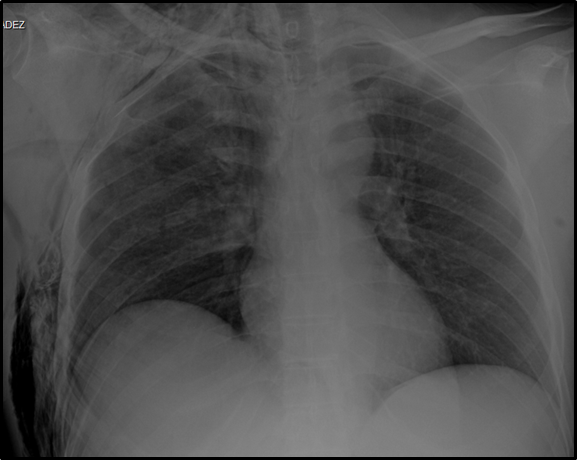

This is a 41-year-old male patient, provided his written informed consent, from and resident of Minatitlán, Veracruz with a history of apparent good health, who was transferred by Red Cross paramedics on July 05, 2019 to the Emergency Department, after suffering a fall from a height of 4 meters in his work area. The diagnosis of polyconcussion was established and the evaluation of cabinet studies identified: distal metaphyseal fracture of the right radius and ulna, intertroncantal fracture of the left femur and costal fractures from the second to the seventh right costal arch; at this time, he was diagnosed as polytrauma/unstable thorax (Figure 1–3).

Figure 3 Rx of radiocarpal articulation AP. Loss of continuity is observed in styloid processes of ulna and proximal fracture stroke of radius.